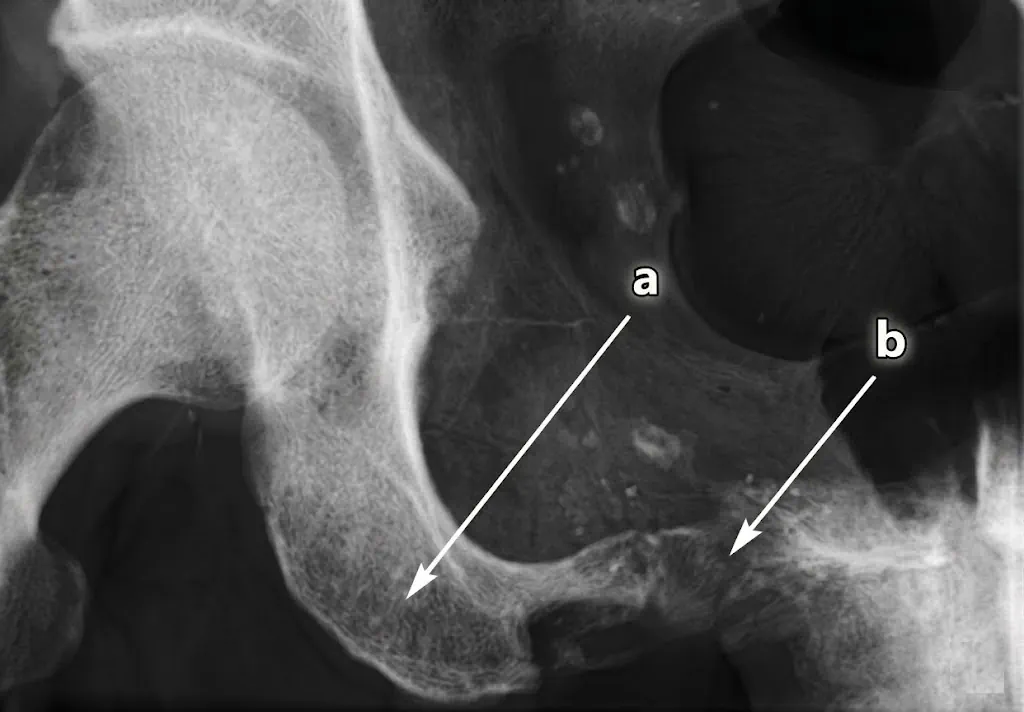

4) Imagen

En imagen, el patrón suele ser agresivo e inespecífico. El punto clave no es “adivinar” el diagnóstico exacto por imagen, sino estadiar y planificar una biopsia segura.

- RX/TC: lesión lítica agresiva, destrucción cortical, reacción perióstica variable y masa de partes blandas.

- RM: define extensión local, compartimentos, neurovasculares y heterogeneidad interna (útil para dirigir muestreo).